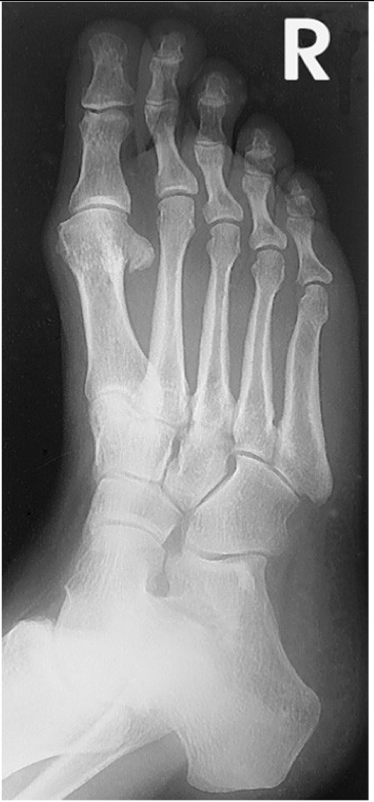

Dorsoplantar (AP) Axial Foot

CR

Angle approx. 10◦ toward heel; centered to base of 3rd metatarsal

Patients with a high longitudinal arch require a greater angle

o 15-degrees

A low longitudinal arch requires less angle

o 5-10 degrees

Evaluation Criteria for AP foot

Entire foot visualized

No rotation of metatarsals

MTP joints generally open

Bases of 1st & 2nd metatarsals separated

Bases of 3rd- 5th overlap

Joint space between 1st & 2nd cuneiform is open

Distal phalanges not overexposed

o May need to use a compensating filter to maintain an uniform image exposure